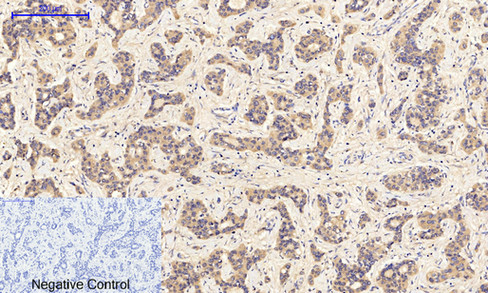

Immunohistochemical analysis of paraffin-embedded Human-liver-cancer tissue. 1,JAK1 (phospho Tyr1034) Polyclonal Antibody was diluted at 1:200(4°C,overnight). 2, Sodium citrate pH 6.0 was used for antibody retrieval(>98°C,20min). 3,Secondary antibody was diluted at 1:200(room tempeRature, 30min). Negative control was used by secondary antibody only.